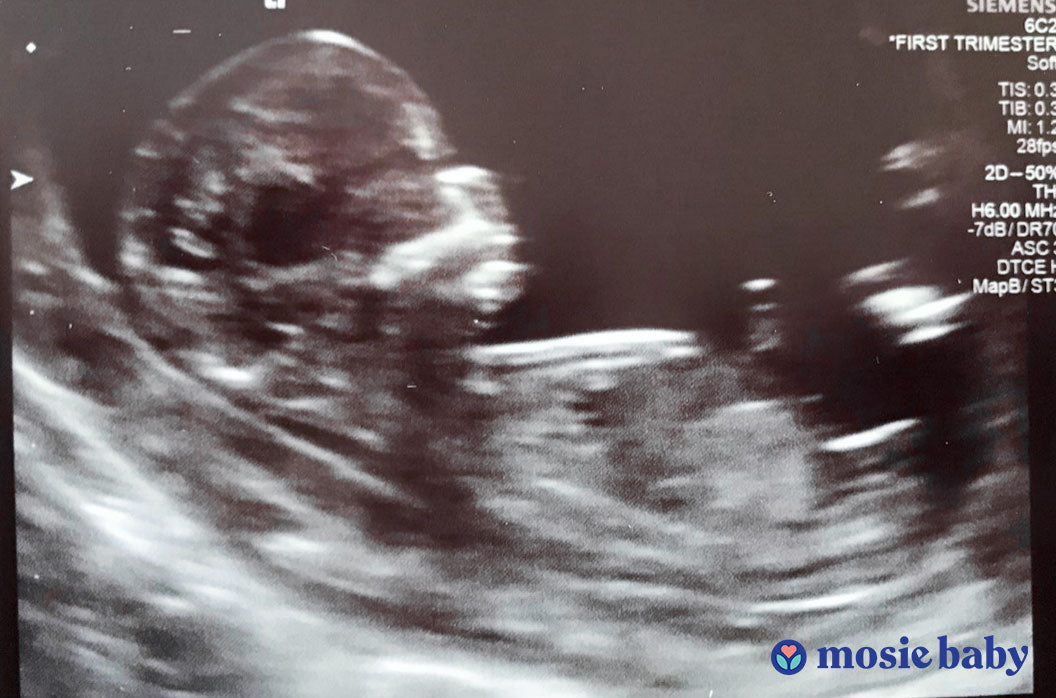

We are now 13 weeks into the pregnancy and cannot wait to meet our little miracle, and all thanks to the amazing people behind Mosie Baby. Would love the opportunity to share our story to help other couples in the same situation we found ourselves in. Xx